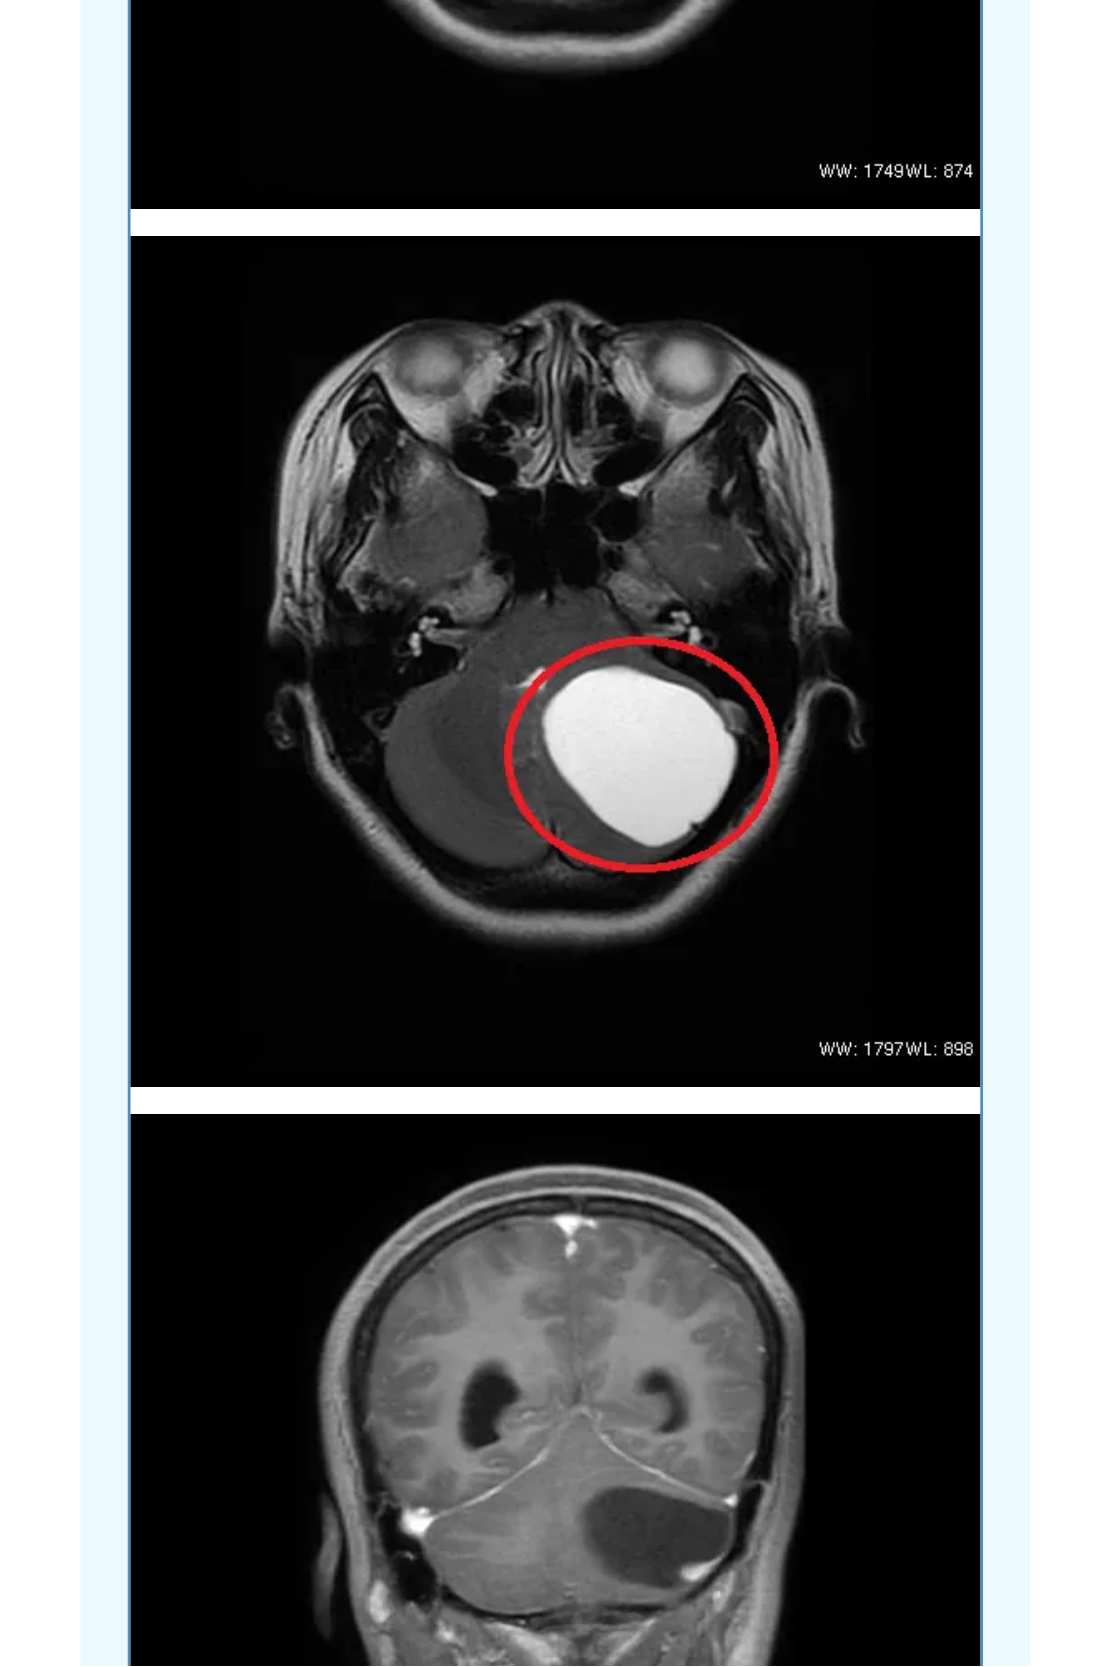

神经导航辅助下改良枕下天幕上入路治疗复杂小脑山坡实质性血管母细胞瘤

血管母细胞瘤( 血管网状细胞瘤、血管网织细胞瘤):为良性肿瘤, 有人认为其起源于血管周围的间叶细胞, 好发小脑中线旁,占颅内肿瘤的1%,后颅窝肿瘤的7%; 主要发生于成人(30~40岁多见);儿童期和老年人少见,男性较女性多见; 分为散发性和家族遗传性两种,后者表现为VHL病。多发者高度提示VHL病。